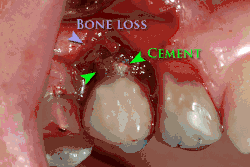

Beyond the possibility of mechanical failure[73] which may be due to poor prosthetic fitment, wear and tear, or user-induced actions such as bruxism, dental implants are also subject to peri-implant mucositis and peri-implantitis, where gum tissue and bone mass around the implant are resorbed, and the implant gradually becomes loose, and has to be removed.[74][75] In addition, although titanium is generally well tolerated by the body, there have been cases where the build-up of titanium particles released by the implant may cause systemic inflammatory response.[76] Because there is no dental enamel on an implant, it does not fail due to cavities like natural teeth. While large-scale, long-term studies are scarce, several systematic reviews estimate the long-term (five to ten years) survival of dental implants at 93–98 percent depending on their clinical use.[2][3][4] During initial development of implant retained teeth, all crowns were attached to the teeth with screws, but more recent advancements have allowed placement of crowns on the abutments with dental cement (akin to placing a crown on a tooth). This has created the potential for cement, that escapes from under the crown during cementation to get caught in the gingiva and create a peri-implantitis (see picture below). While the complication can occur, there does not appear to be any additional peri-implantitis in cement-retained crowns compared to screw-retained crowns overall.[77] In compound implants (two stage implants), between the actual implant and the superstructure (abutment) are gaps and cavities into which bacteria can penetrate from the oral cavity. Later these bacteria will return into the adjacent tissue and can cause periimplantitis.